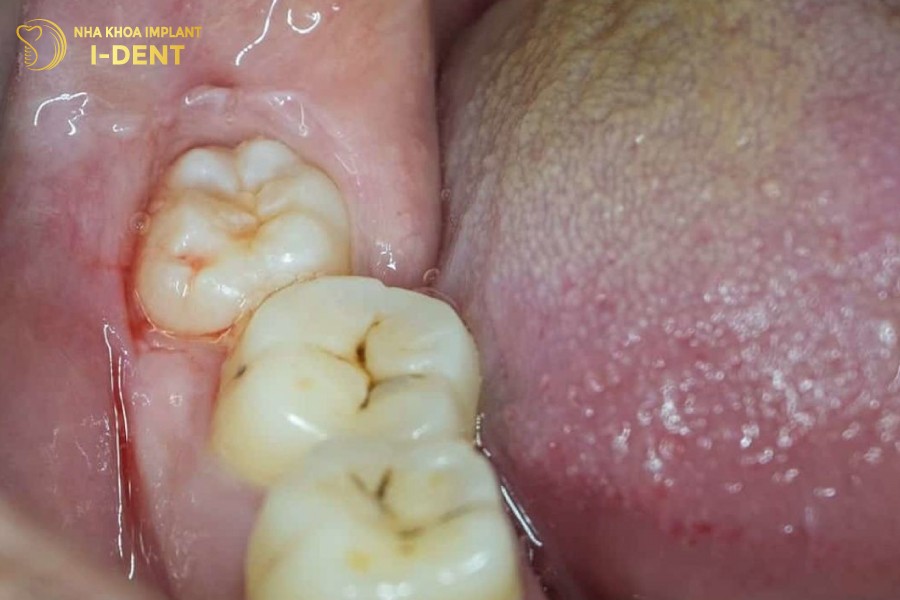

Răng khôn mọc lệch ra má là tình trạng răng khôn mọc lệch theo hướng đưa ra ngoài phía má. Nguyên nhân là do răng khôn mọc lên sau cùng, khi tất cả các răng khác đã phát triển đầy đủ nên thường không còn đủ vị trí trên cung hàm, bắt buộc răng khôn phải mọc chen chúc và tạo ra tình huống mọc lệch ra phía má.

Một trong những biến chứng dễ nhìn thấy nhất chính là dễ cắn vào má khi ăn nhai. Vài lần như vậy sẽ khiến vùng má bị lở loét và mưng mủ. Khi răng khôn mọc sẽ mang lại cảm giác đau nhức, khó chịu và sưng tấy. Làm ảnh hưởng đến công việc và cuộc sống sinh hoạt hằng ngày.

Răng khôn mọc lệch ra má